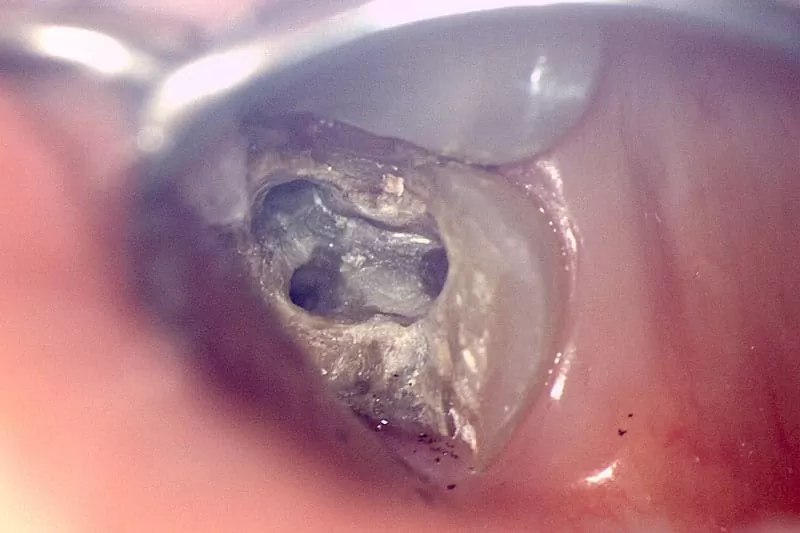

顯微根管清創完成

我的牙醫師-沈庭帆醫師,是位可愛又幽默的媽咪,非常詳細為我解說目前牙齒的狀況,並分析上一次根管治療未成功的問題,牙齒為了做完假牙後能安心使用,根管勢必重做治療,而這次的根管治療有別以往的經驗,是採用顯微根管治療,透過顯微鏡精準醫治,能夠完整填補神經取出後缺口,不讓細菌有孳生的空間,針對二次根管治療或是細微難找的根管,盡到最大辦法醫治,是非常進步的醫療技術。因為醫師透明化治療解說,讓我對療程不會有未知的恐懼感,反而能更寬心治療。另外療程的安排及費用,也都有櫃檯小姐清楚的說明及同意書簽名,確保我非常了解自己的療程,避免後續產生不必要的疑慮。